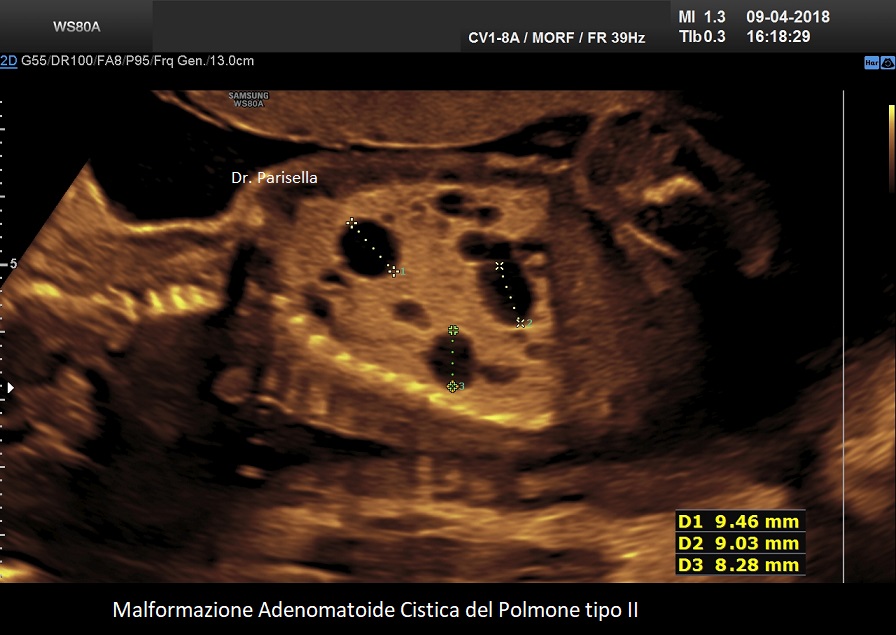

MACP tipo II: è caratterizzato da numerose piccole cisti di diametro < 2,0 cm.;

. Le lesioni di tipo II si verificano in circa il 40% dei casi e sono costituite da numerose piccole cisti (< 2,0 cm) mescolate con aree di aumentata ecogenicità all'ecografia. La prognosi dipende dalla gravità della lesione e dalla sua associazione con altre malformazioni fetali. Esiste una associazione tra anomalie congenite e CCAM di tipo II, le principali delle quali sono genitourinarie, come la disgenesia o l'agenesia renale, e cardiache, come la tetralogia di Fallot e il tronco arterioso; altri includono l'ernia diaframmatica e le anomalie muscoloscheletriche. Un importante studio, considerato una delle più grandi coorti di casi, conclude che le CCAM microcistiche e macrocistiche presentano entrambe decorsi e prognosi perinatali simili (Chen Y et al., 2021).

La malformazione adenomatoide cistica del polmone (CAM) ha una storia naturale variabile che può evolvere in idrope o regredire. Non sono disponibili criteri per determinare quali lesioni crescerebbero e svilupperebbero idrope rispetto a quelle la cui crescita si stabilizzerebbe o regredirebbe. Per calcolare il rischio di sviluppare l’idrope fetale è stato proposto l’utilizzo del rapporto volumetrico CAM Volume Ratio (CVR) cioè il rapporto tra volume della MACP e la circonferenza cranica (Crombleholme TM et al., 2002). Il volume della MACP viene calcolato moltiplicando i tre diametri della massa x 0,52.  I feti con CVR inferiore o uguale a 1,6 sono considerati a basso rischio di sviluppo di idrope e quelli con CVR maggiore di 1,6 sono considerati a rischio aumentato per lo sviluppo dell'idrope. Per valori di CVR > 1,6 il rischio di sviluppare l'idrope è del 75%, mentre per valori di CVR < 1,6 il rischio scende al 16%.

Si presenta come una massa occupante spazio di solito unilaterale in più del 95% dei casi e solitamente coinvolge un lobo o segmento del polmone; nella sua evoluzione determina dislocazione del mediastino e del cuore. L'ecostruttura distingue due forme: una forma multicistica  caratterizzata dalla presenza di multiple cisti di varia grandezza (tipo I e II) e una forma microcistica (tipo III) corrispondente alla variante solida.